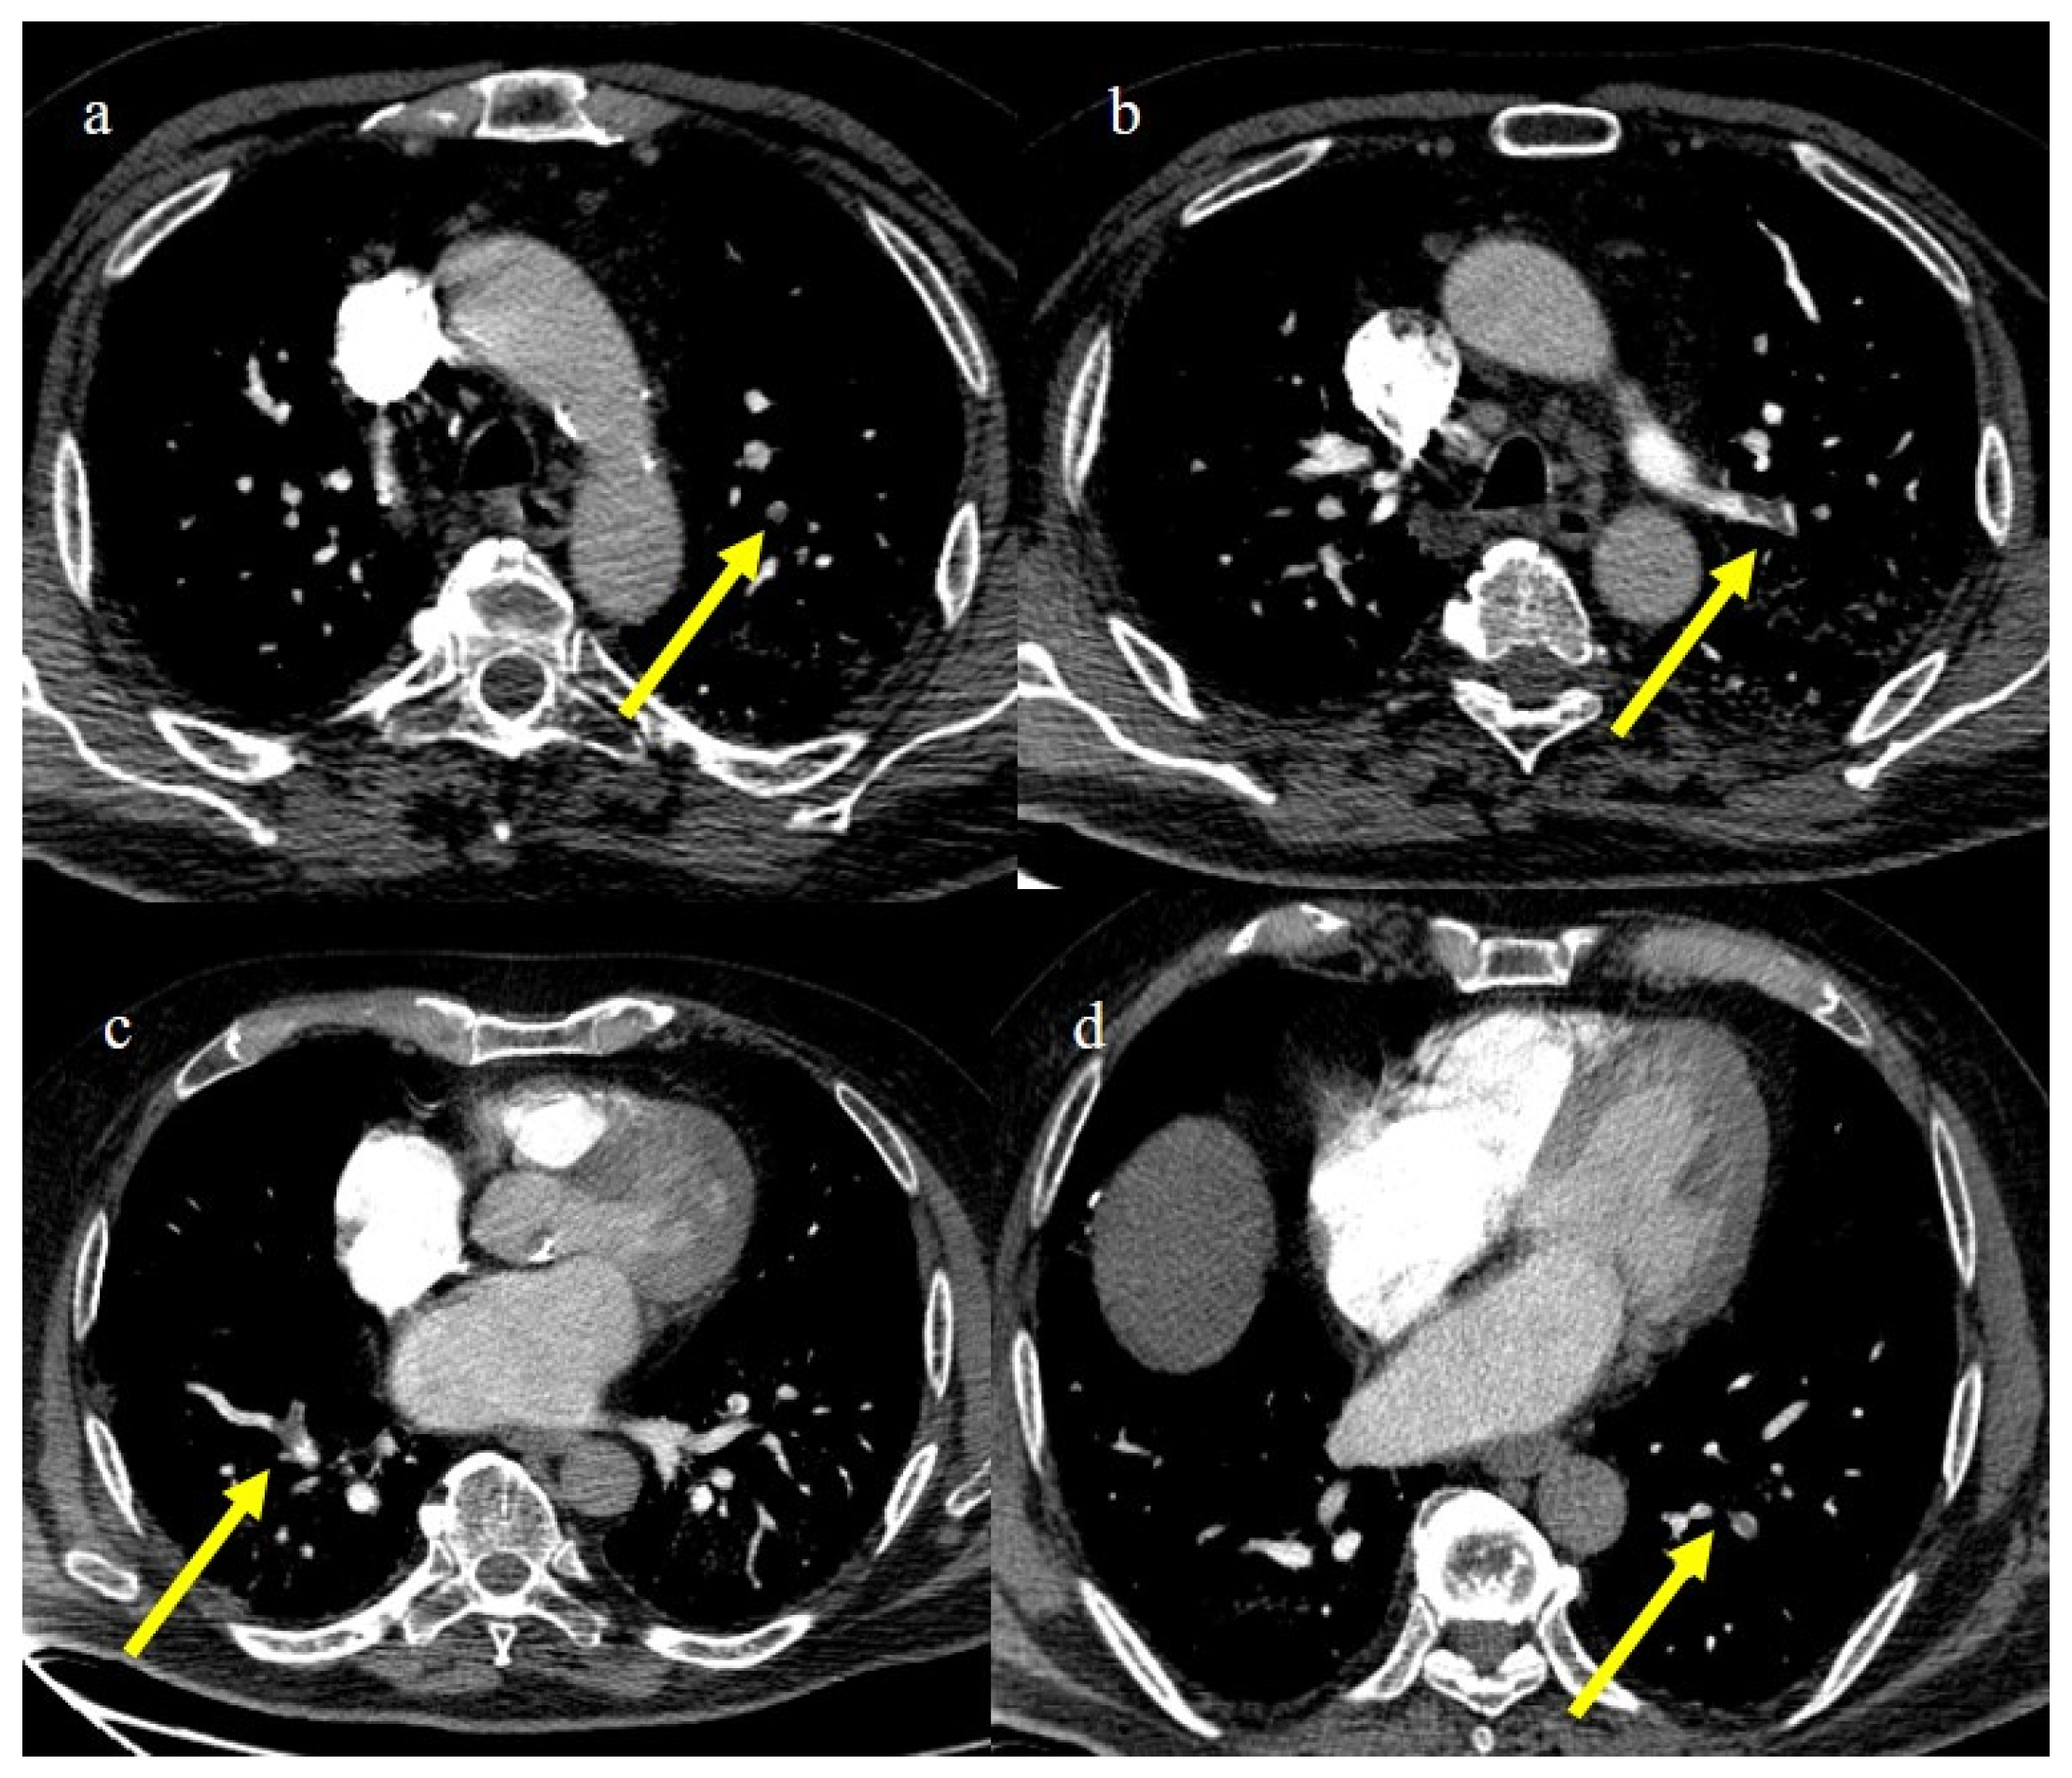

3.3.4. Pulmonary Thromboembolism

4. Vascular Abdominal Extrapulmonary Complications